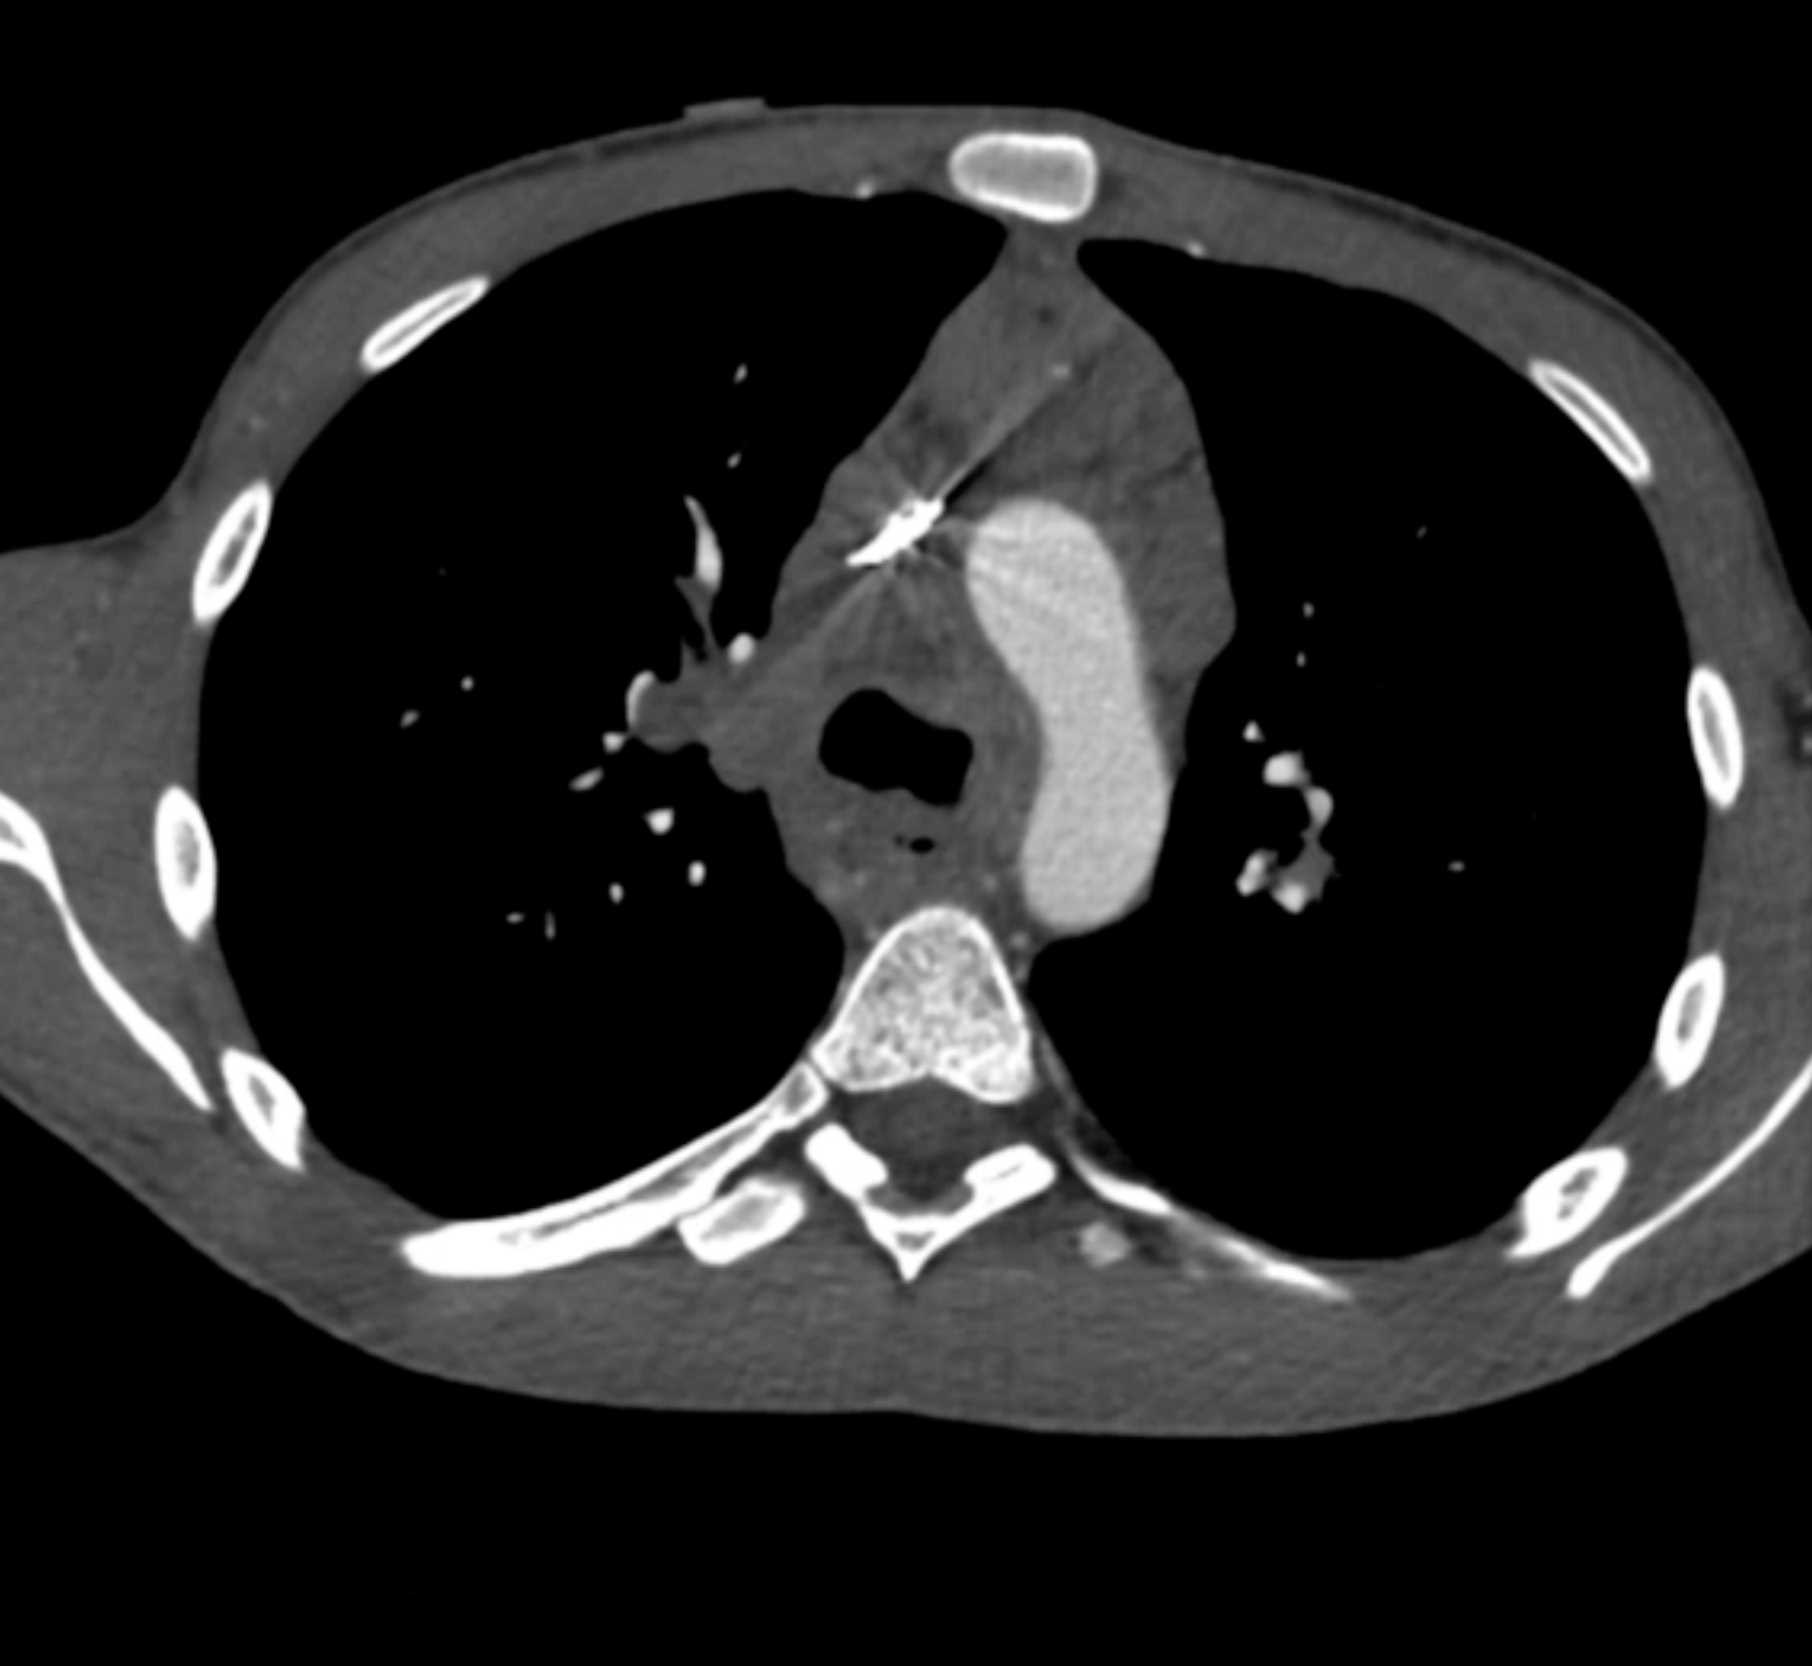

Primary Spindle Cell Carcinoma of the Right Ventricle